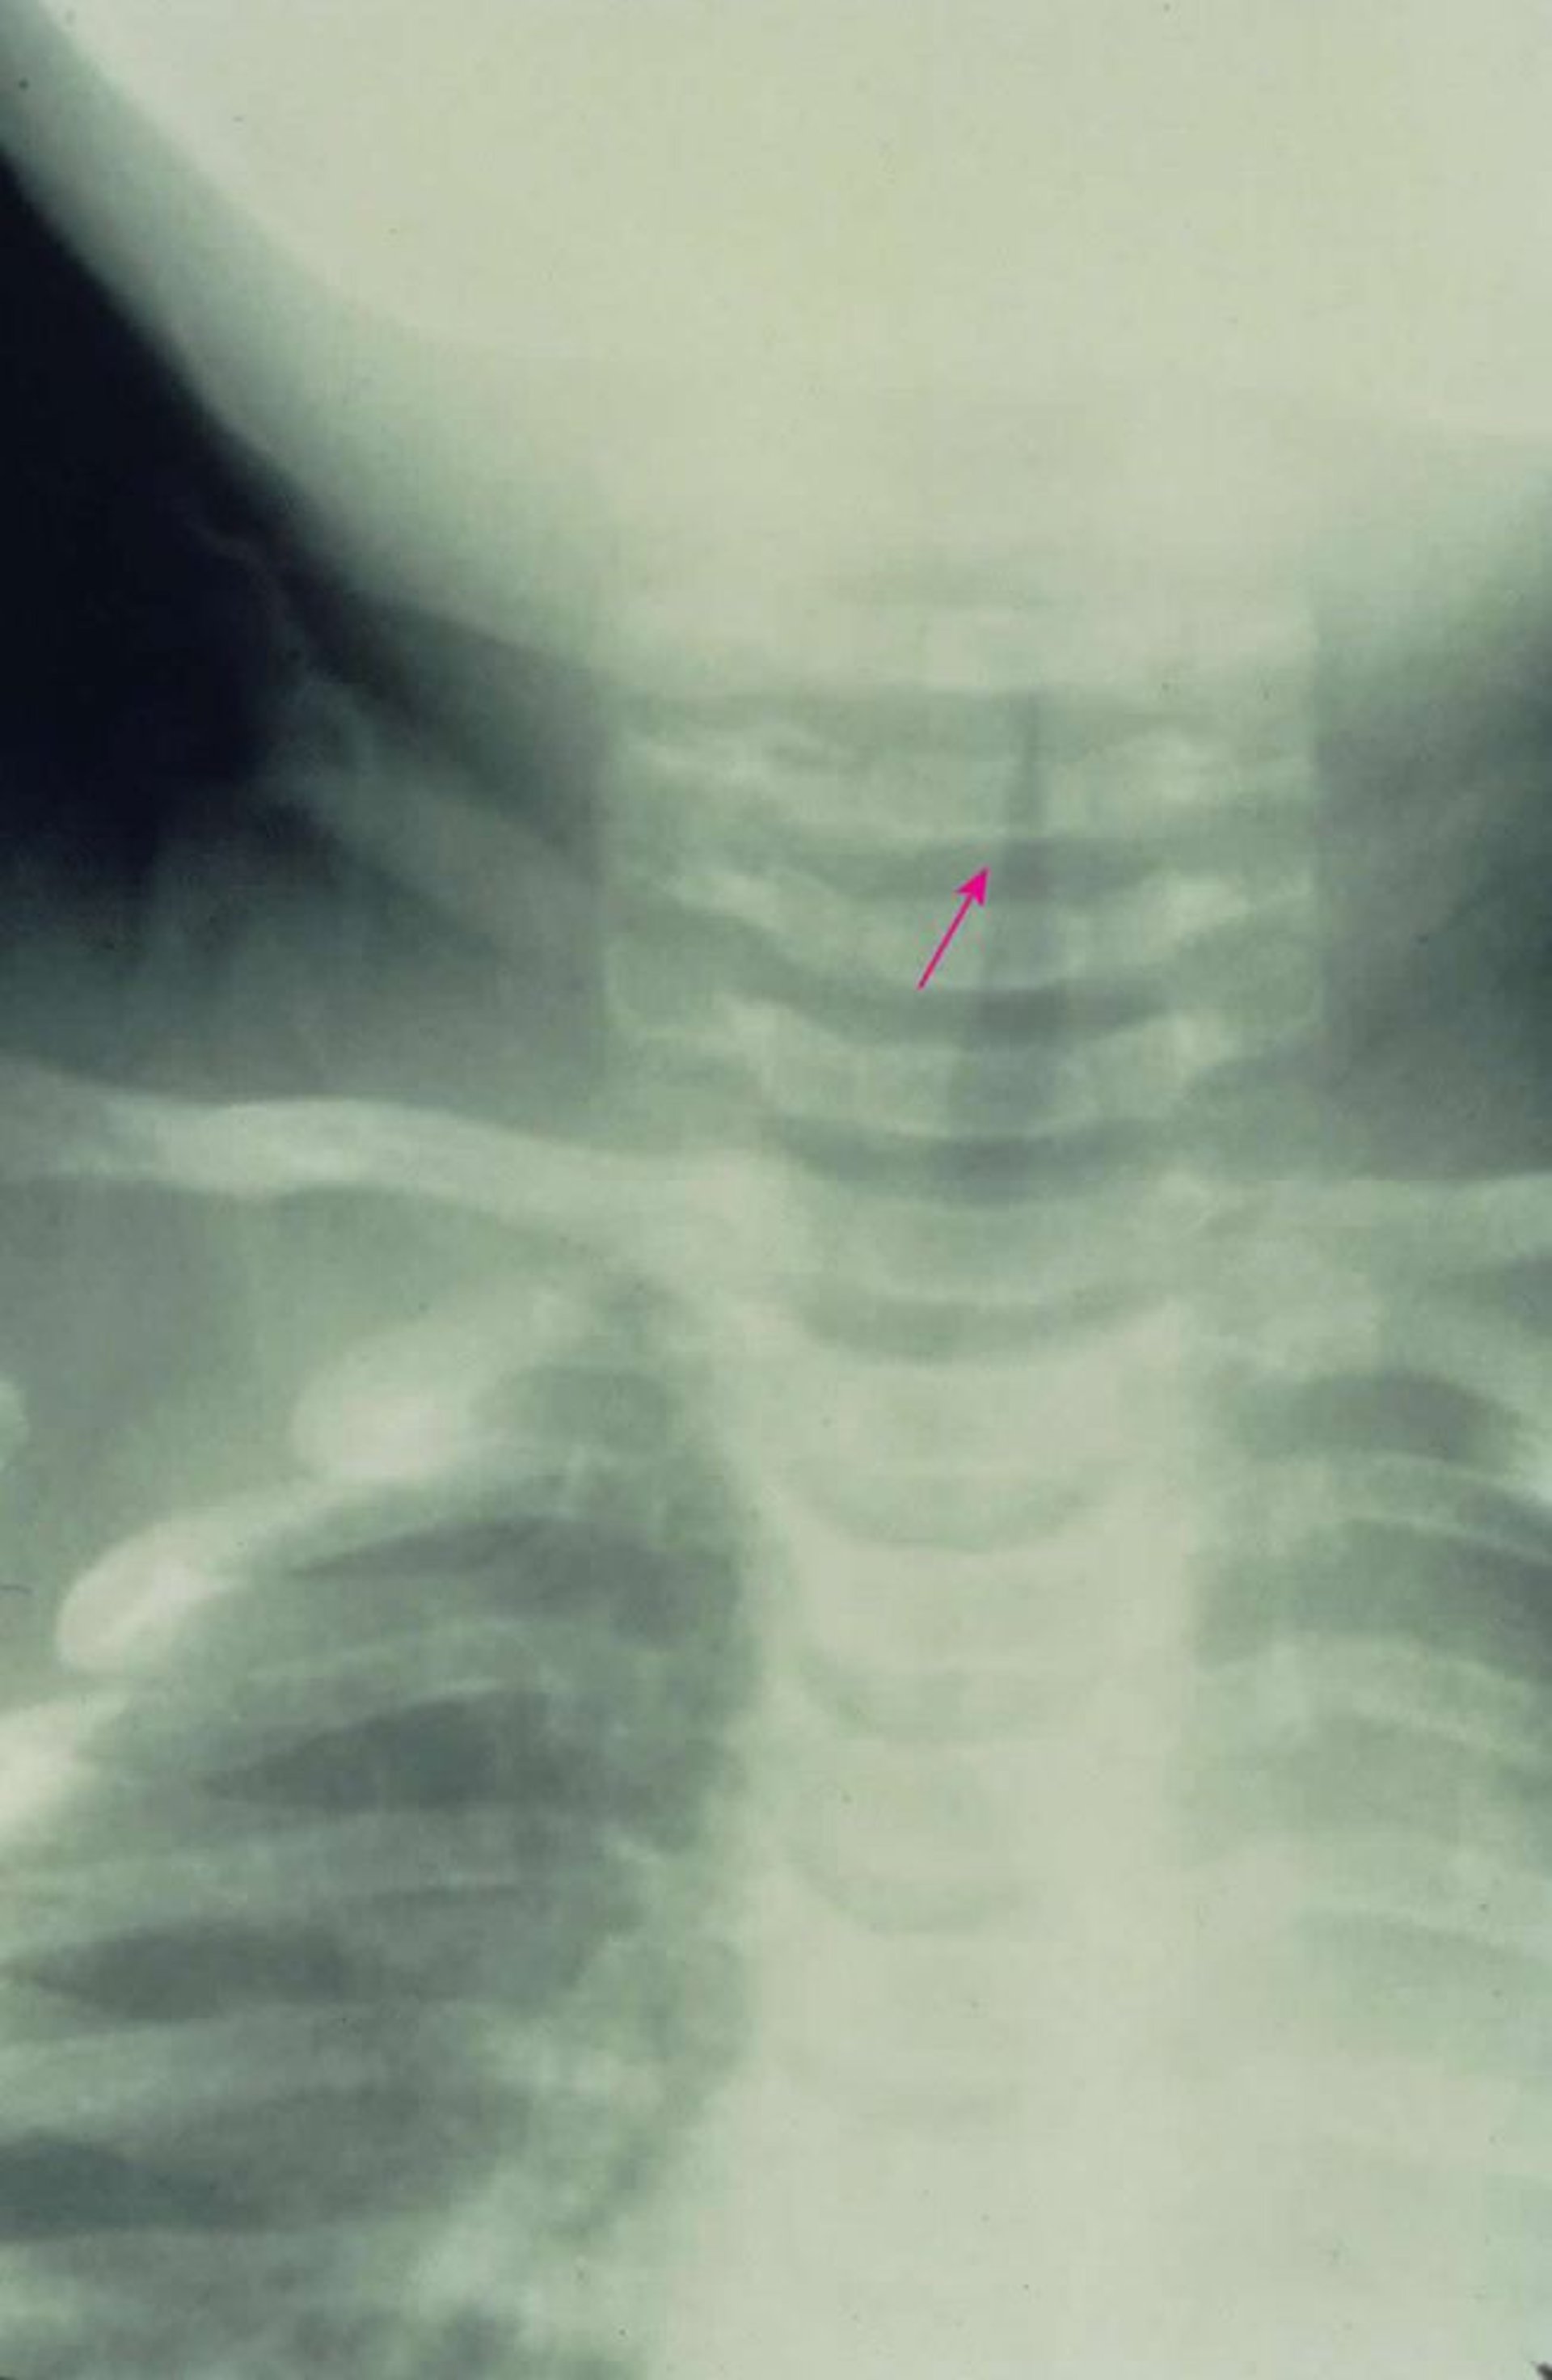

Viêm thanh khí phế quản dưới thanh môn

Phim chụp X-quang trước-sau cho thấy đặc trưng là hẹp đường thở dưới thanh môn (dấu hiệu gác chuông [mũi tên]) do viêm thanh khí phế quản.

Hình ảnh do bác sĩ Clarence T. Sasaki cung cấp.